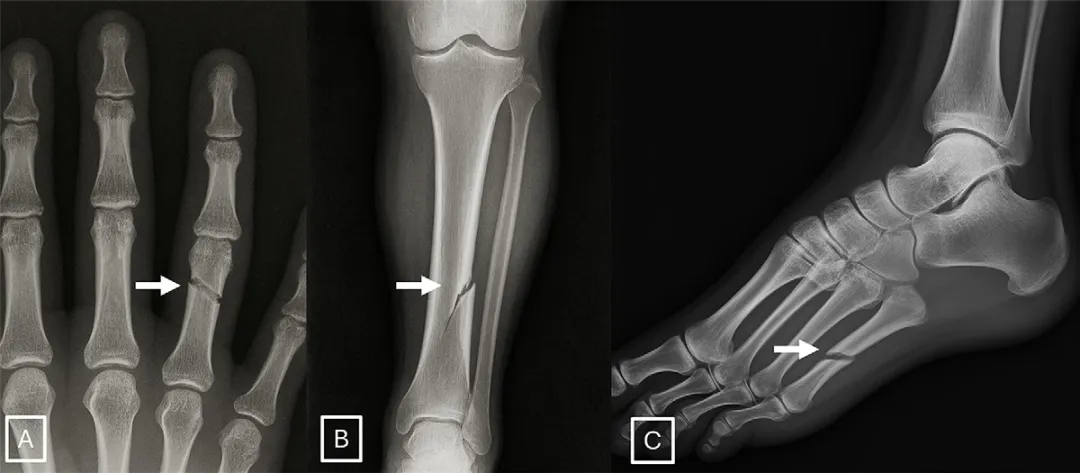

他们首先利用ChatGPT-4o,根据包含解剖部位、投照方式、目标异常(如骨折、肿瘤)等信息的文本提示,生成了77张合成X光片,涵盖胸部、脊柱和四肢。同时,从公开数据库和机构内数据库中匹配了77张真实的X光片,共同组成第一个数据集。

过度的对称性:AI倾向于生成完全对称的解剖结构,例如脊柱完美笔直,除非特意提示“脊柱侧弯”。 均匀的纹理与噪声:真实X光片的颗粒噪声分布是不均匀的,而AI生成的图像噪声往往过于均匀一致。 不自然的软组织纹理:肌肉、脂肪等软组织的灰度过渡有时显得 subtly(微妙地)不自然。 过于光滑的骨骼:骨皮质的边缘异常光滑,厚度均匀,缺乏真实骨骼那种自然的微小不规则和纹理。 “理想化”的骨折线:AI生成的骨折线往往异常清晰、平滑,有时甚至是单皮质的(仅一侧骨皮质断裂),这与真实创伤中复杂、粗糙的骨折形态不同。